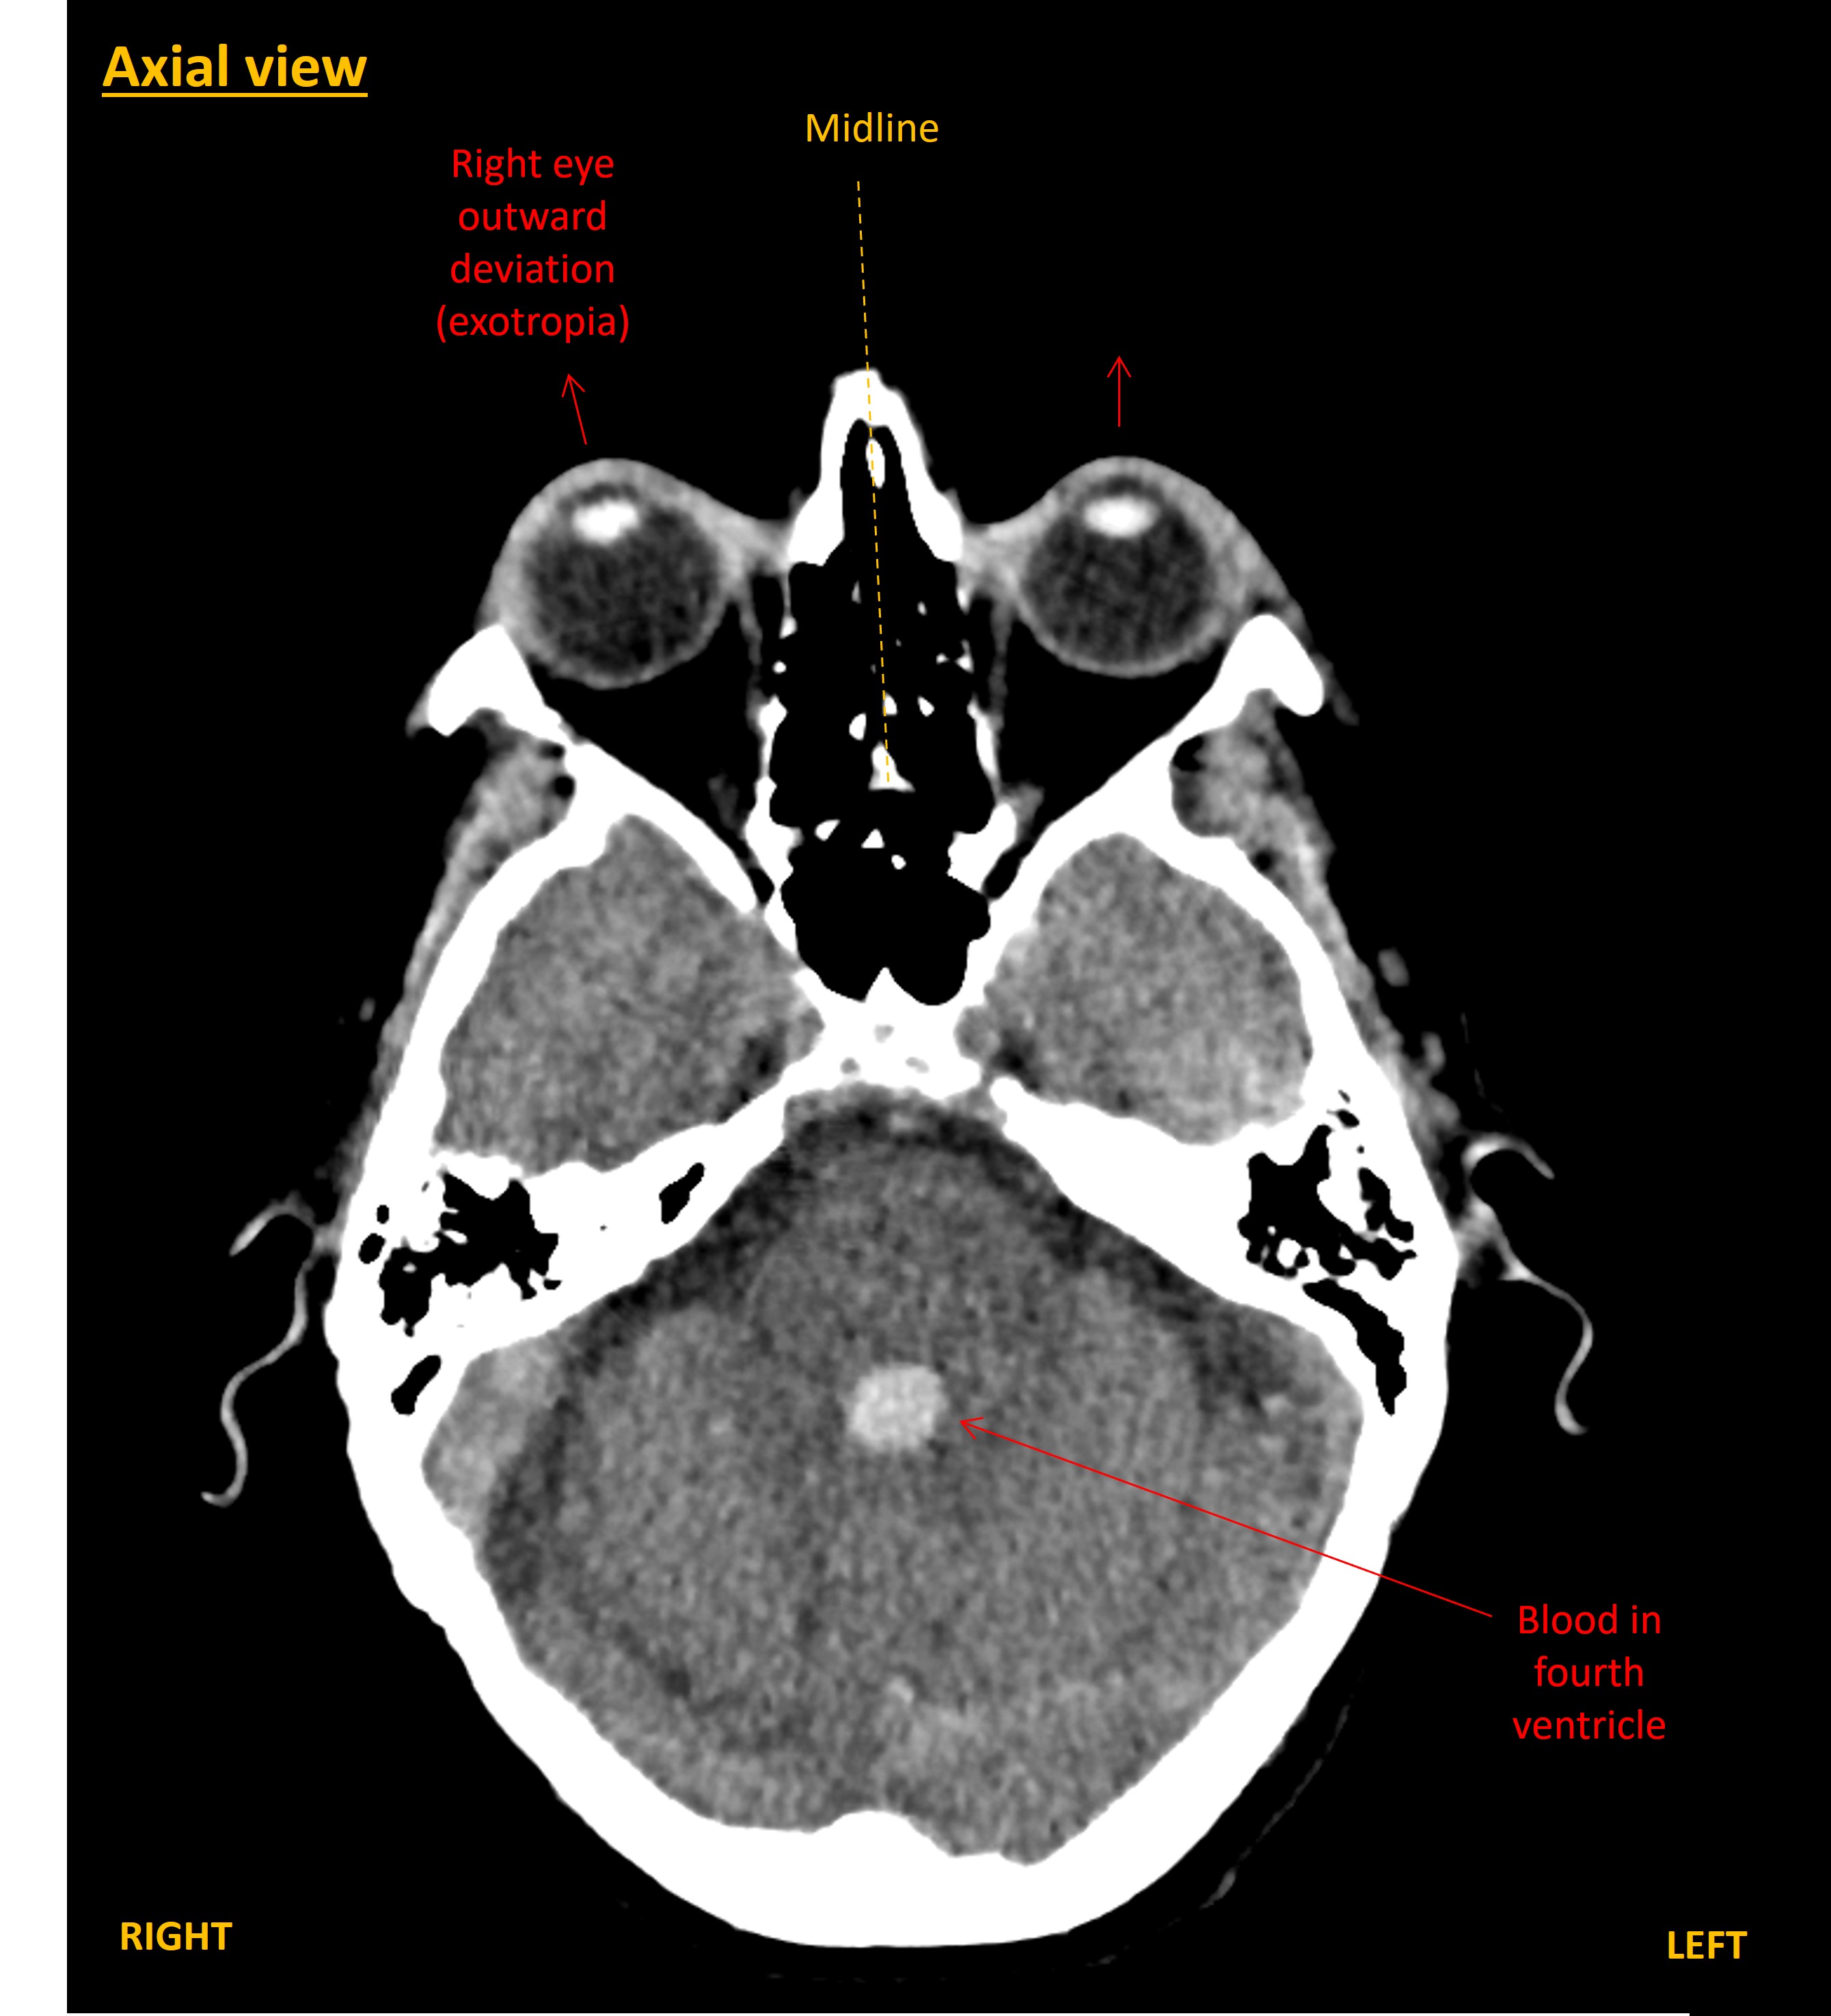

A CT brain was performed immediately. This showed a large right-sided intracerebral haemorrhage within the frontal and parietal lobes. The blood was causing mass effect with midline shift towards the left, and right uncal herniation. The haemorrhage had extended into the ventricles, including down to the fourth ventricle, with hydrocephalus.